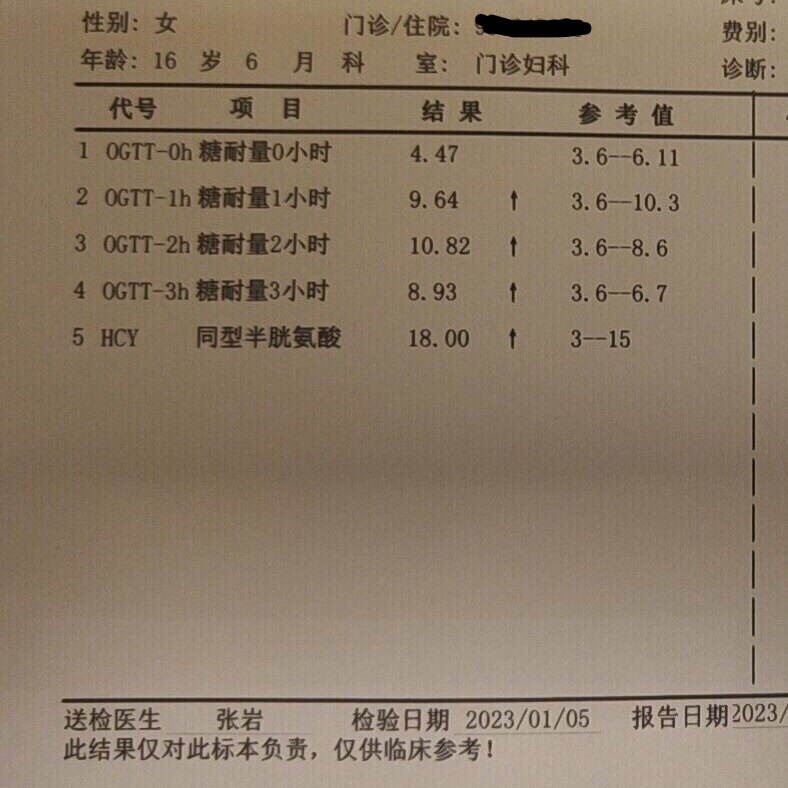

糖耐量受损和高同型半胱氨酸血症

这是一位16岁的高中生,12岁初潮,月经不规律,这次是因为闭经四年前来就诊。根据她的病史症状、一系列化验和超声检查结果,我给她下的诊断是:糖耐量受损,胰岛素抵抗,高同型半胱氨酸血症,青春期多囊卵巢综合征。她的25羟基维生素D只有14.45ng/ml,所以我还诊断她维生素D缺乏。

这个才16岁的花季少女,她的同型半胱氨酸这么高(≧10μmol/L为高血同),估计她的动脉粥样硬化已经起步n年了。如果现在不开始加以控制的话,估计她在40岁左右就会出现心梗或脑梗。